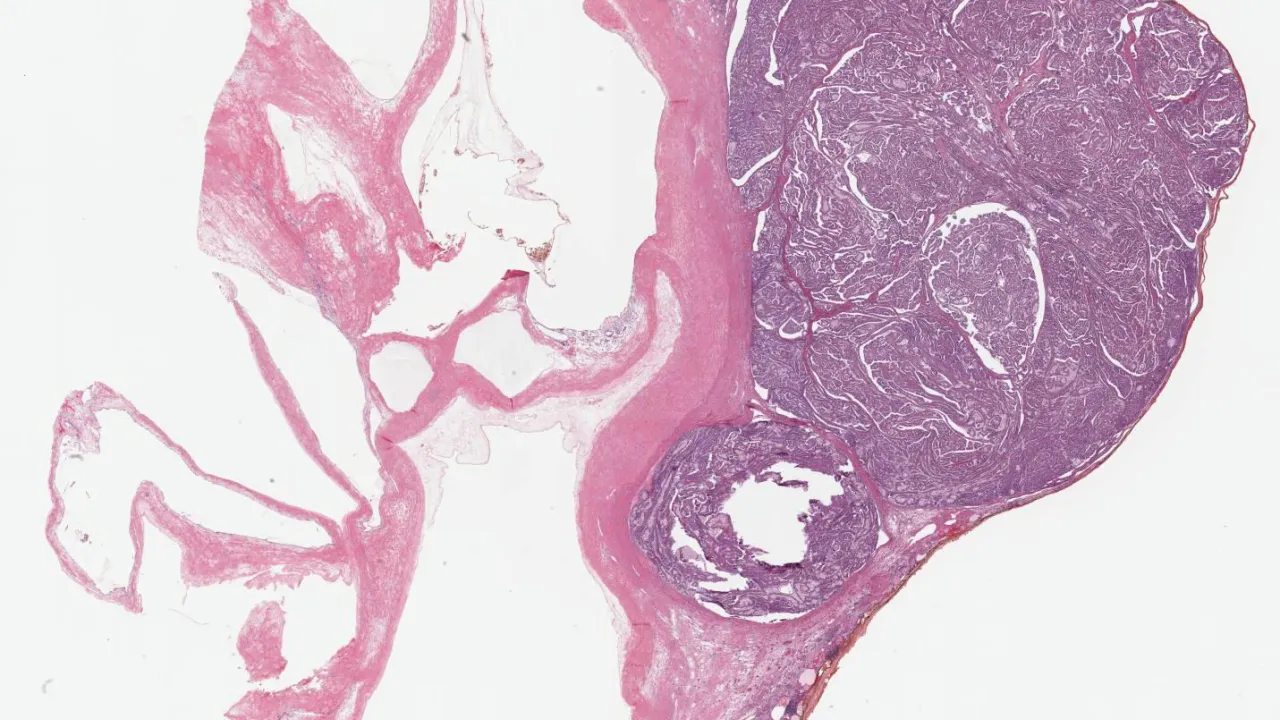

Breast, Myofibroblastoma, H&E stain